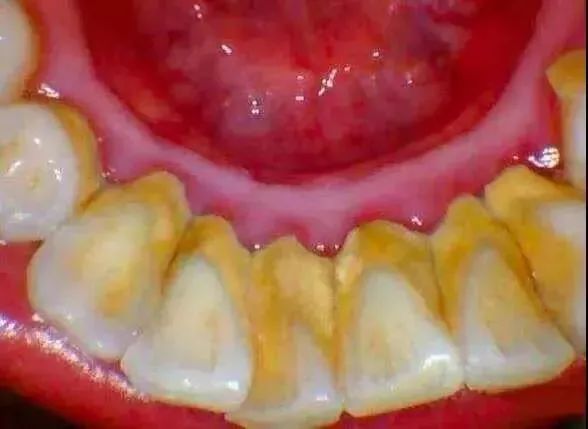

牙菌斑是附着在牙面上,特别是牙颈部的细菌性团块。这些团块因钙化而变硬成为牙石,菌斑和牙石是引起牙周炎的主要因素。

牙结石是附着在牙齿表面的硬性斑块,其外形似黄色干石灰块,较坚硬,易使牙龈出血。牙石上附着大量的菌斑。

牙结石

洗牙前后对比